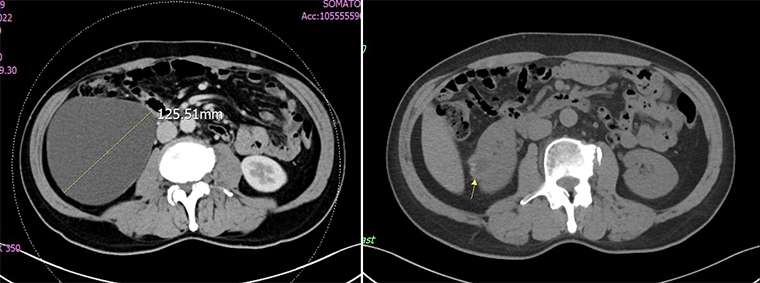

62歲的吳先生,因右側腰痠腰痛持續3週而前往奇美醫療財團法人奇美醫院泌尿外科主任黃冠華門診就診,發現右側腎臟有1顆直徑達12公分的腎盂旁囊腫。吳先生選擇接受自然孔道無創腎內手術,手術後,吳先生於第2天便順利出院,腰痠腰痛的症狀完全消失,恢復日常生活,甚至開心地抱起了孫子也不會感到不適。

【NOW健康 翁靖祐/台南報導】62歲的吳先生,因右側腰痠腰痛持續3週而前往奇美醫療財團法人奇美醫院泌尿外科主任黃冠華門診就診,發現右側腎臟有1顆直徑達12公分的腎盂旁囊腫。吳先生選擇接受自然孔道無創腎內手術,手術後,吳先生於第2天便順利出院,腰痠腰痛的症狀完全消失,恢復日常生活,甚至開心地抱起了孫子也不會感到不適。